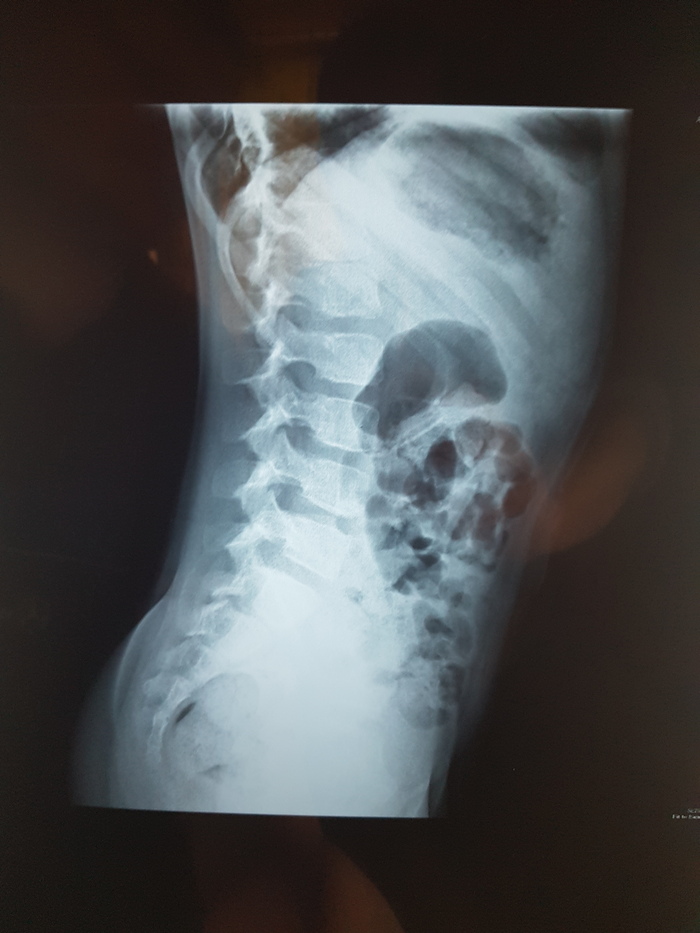

Нужна помощь вертебролога

Добрый день, сообщество! Нужна помощь, совет, консультация. Что угодно, что-бы мне понять что делать дальше. У ребенка при проведении рентгенографии в районой поликлинике выявили полупозвонок Th9.

В поликлинике хирург-ортопед настоятельно рекомендовал искать специалистов вертебрологов-ортопедов.  На пикабу встречаются совершенно разные специалисты, и может есть вертебрологи, ортопеды, которые смогут подсказать куда нам лучше обращаться. Насколько я понимаю, речь идет про операцию. Или возможны варианты? А если операция, то где ее могут сделать? И сколько примерно может стоить? И можно ли ее провести по ОМС или по квоте.

Вобщем, нуждаюсь в любой помощи, совете, консультации. Спасибо. Без рейтинга

Р.с. ребенку 7,5 лет. Территориально Москва